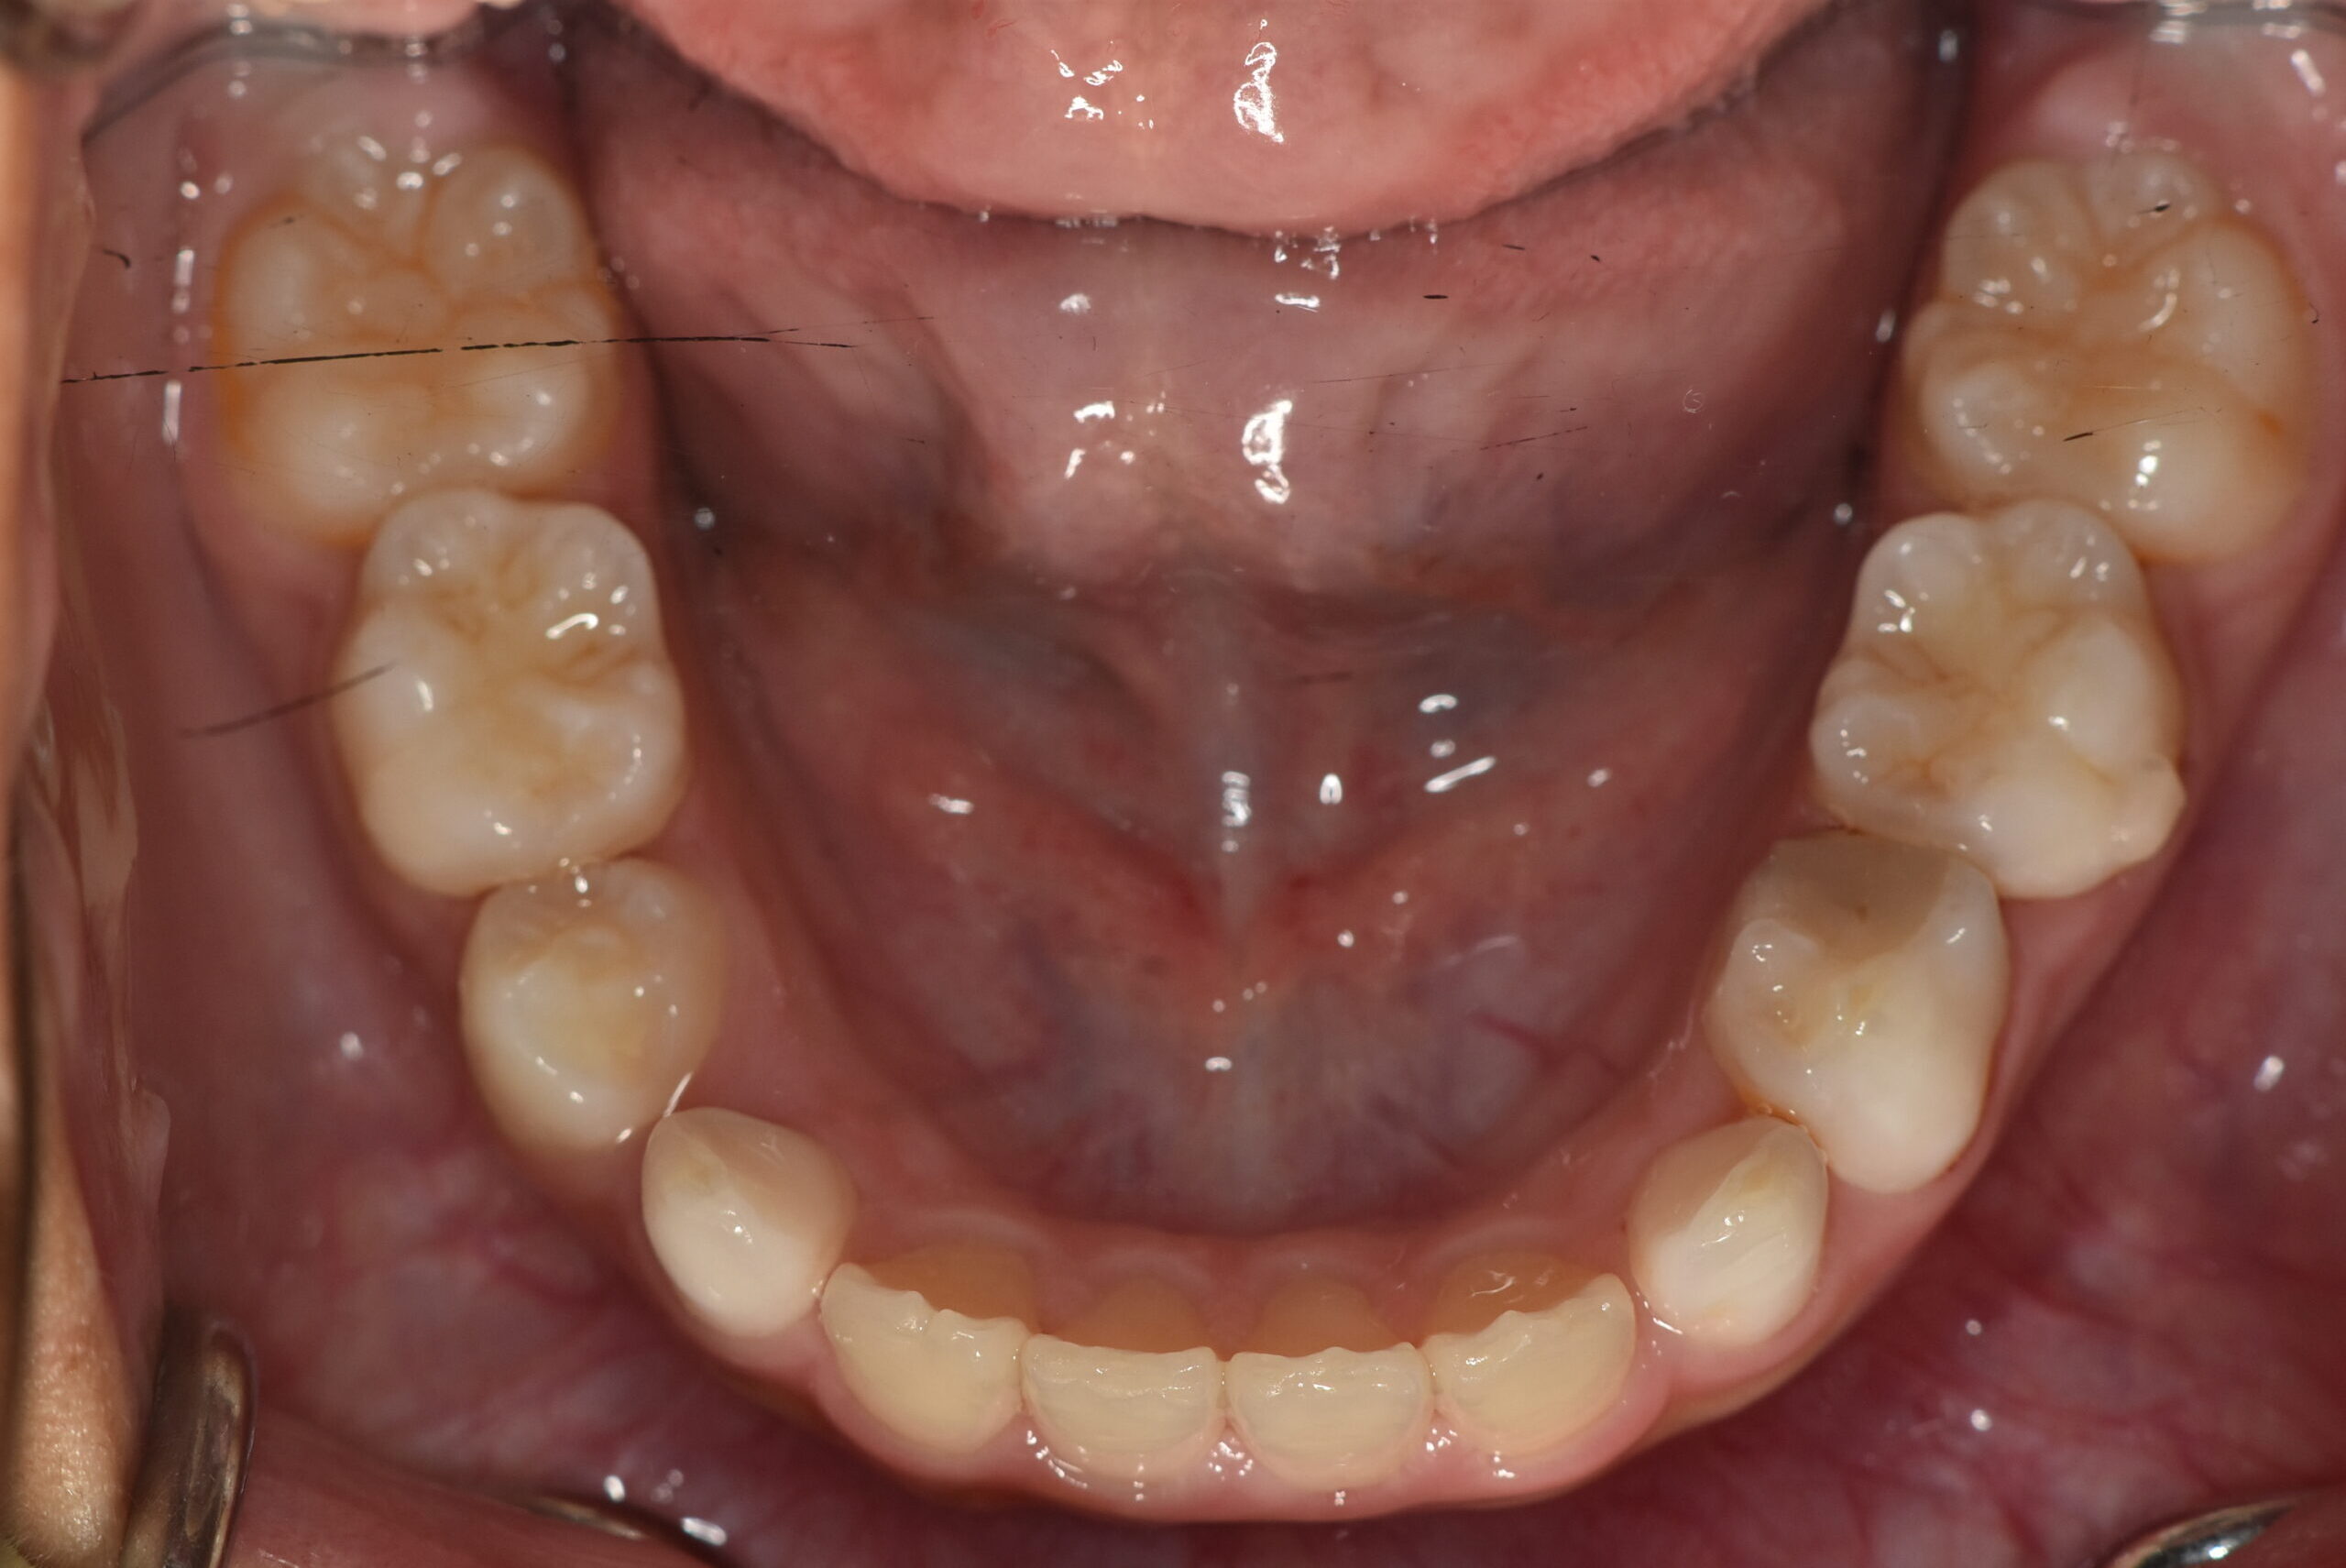

| 治療内容の詳細 | 初診時9歳3ヶ月の男児で、前歯が磨きにくく虫歯になりやすいことを気にされ来院されました。 検査の結果、前歯部叢生を伴うアングルⅠ級不正咬合と診断しました。 治療としてはマウスピース矯正(インビザラインファースト)で配列を行い、上下顎の側方拡大により永久歯の萌出スペースを確保しました。 治療期間は、1年6ヶ月でした。 今後、永久歯(側方歯)の生え変わりまで経過観察を行います。 |